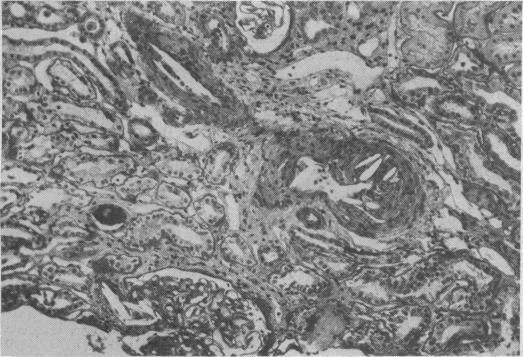

Cholesterol embolism in a renal graft after treatment with streptokinase.

Br Med J (Clin Res Ed). 1988 Feb 6;296(6619):394-5. doi: 10.1136/bmj.296.6619.394-a.